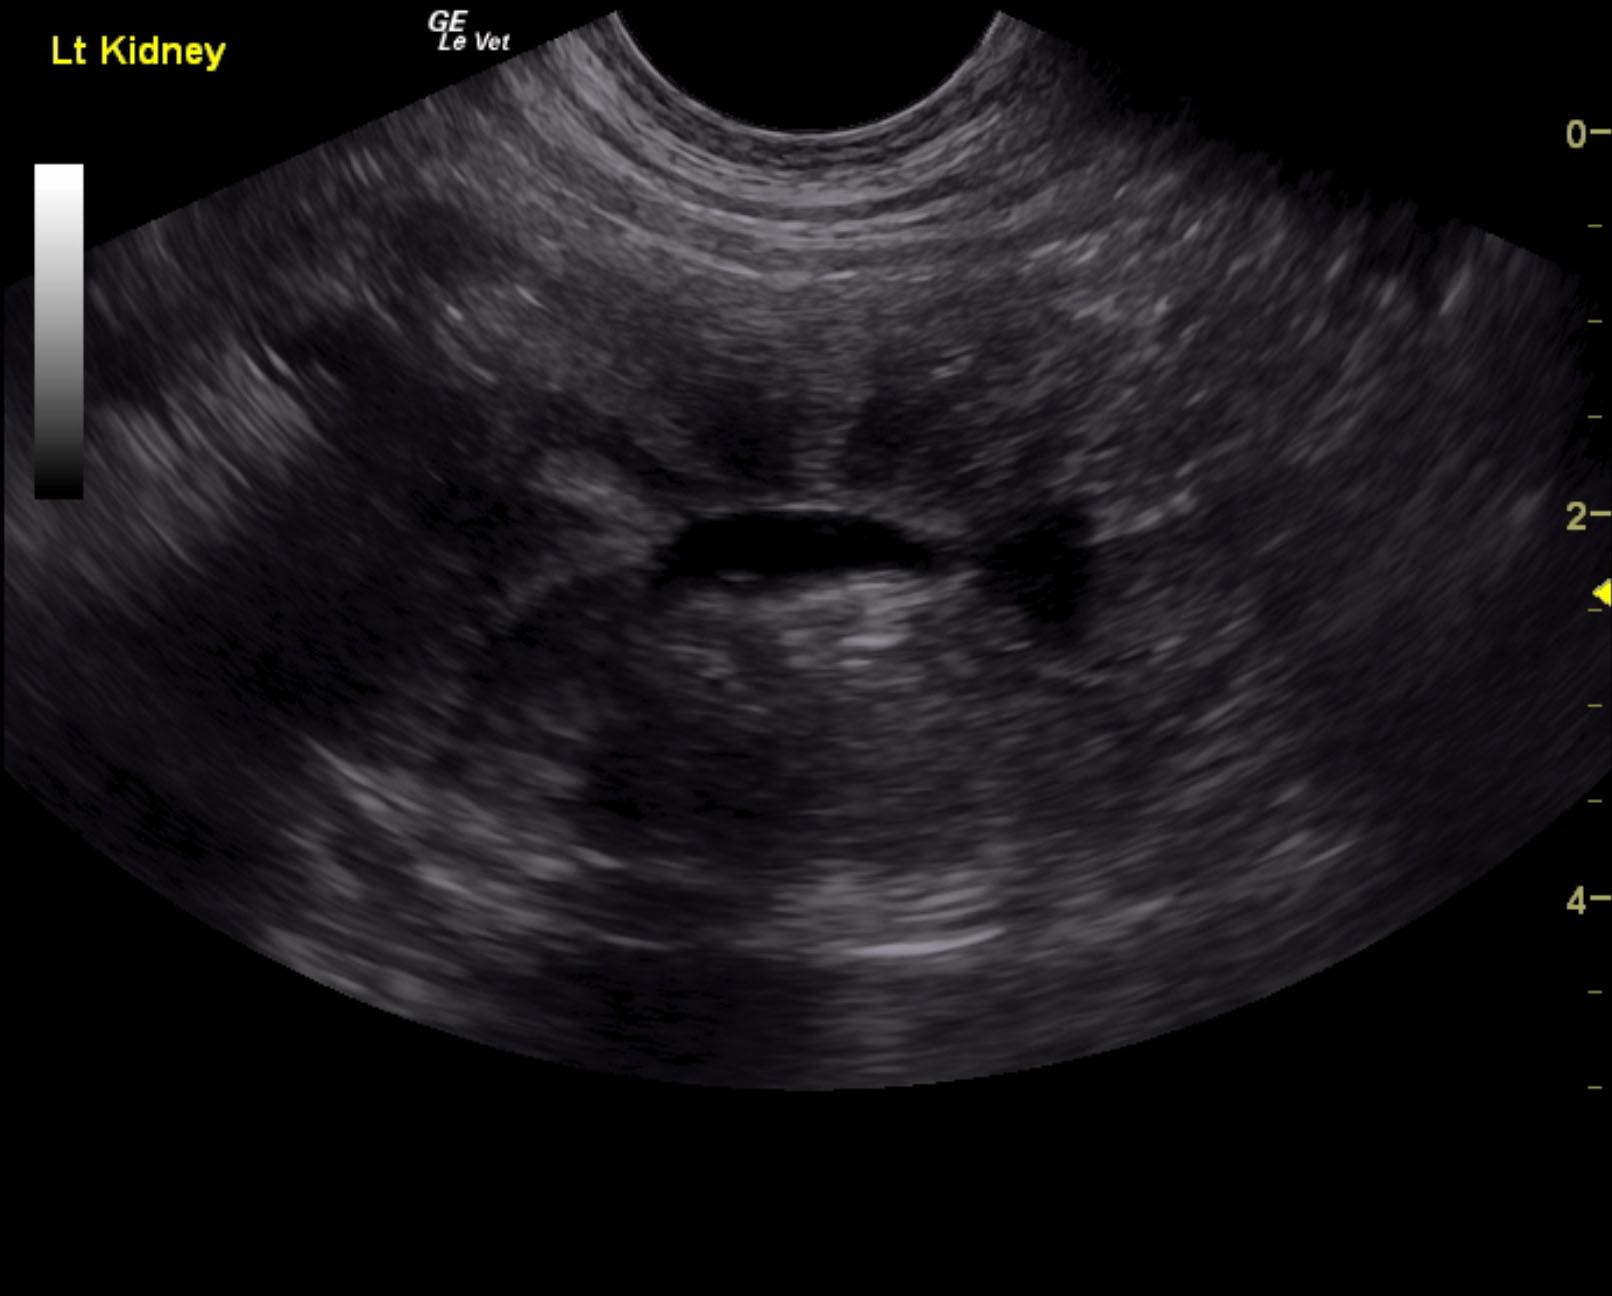

Both kidneys in this patient presented significant, dysplastic changes with cortical irregularity and disruption of the corticomedullary structure. A significant amount of microinfarctions and hyperechoic areas of mineralization and fibrosis as well as cortical cysts were noted. Color flow assessment of the renal cortices was significantly subnormal. This is consistent with chronic disease. The left kidney measured 5.08 cm. The right kidney presented pyelectasia that measured 0.76 cm. The right kidney measured 5.04 cm.